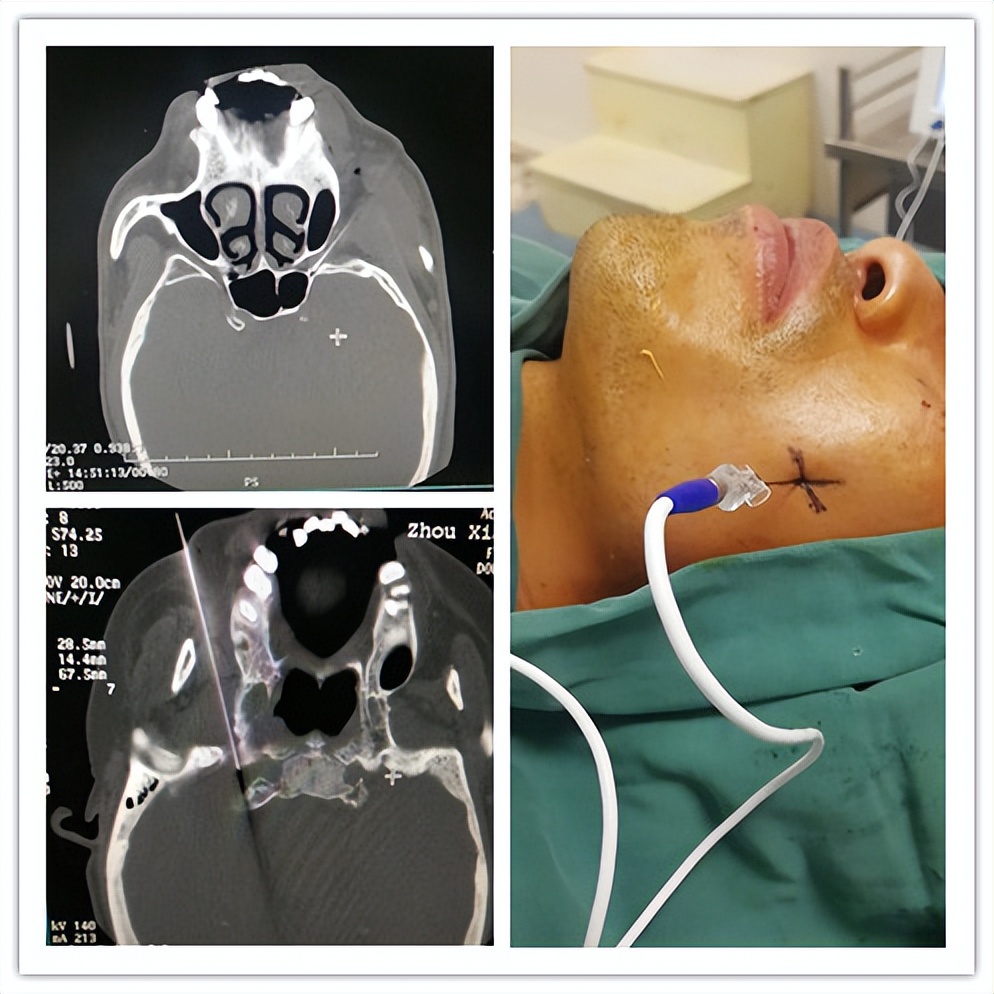

(三叉神经痛:三叉神经射频)